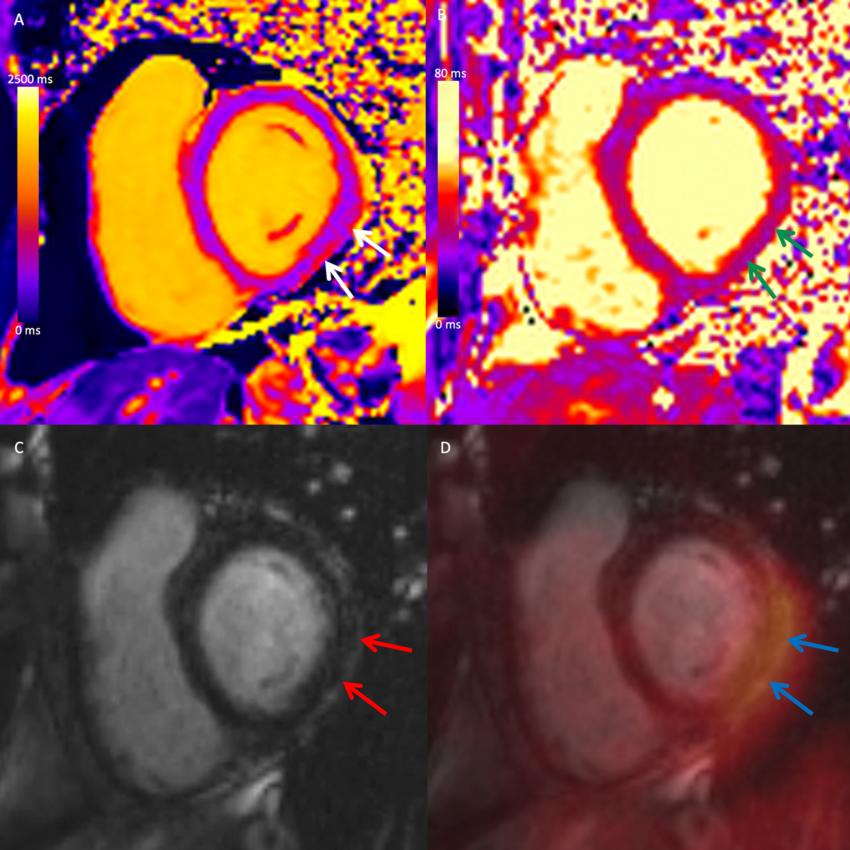

Figure 4. Cardiac PET/MRI in a Participant with Myocarditis after COVID-19 Vaccination. Combined cardiac fluorine 18 fluorodeoxyglucose (FDG) PET/MRI in a symptomatic female participant between 41-50 years of age two months after a diagnosis of myocarditis following COVID-19 vaccination. Short-axis mid-ventricular native (A) T1 and (B) T2 maps demonstrate high T1 and T2 values in the subepicardial inferior and inferolateral wall (white and green arrows, respectively). (C) Short-axis late gadolinium enhancement (LGE) image demonstrates corresponding subepicardial LGE (red arrows). (D) Fused LGE and FDG PET image demonstrates corresponding focal FDG uptake (blue arrows), in keeping with myocardial inflammation.